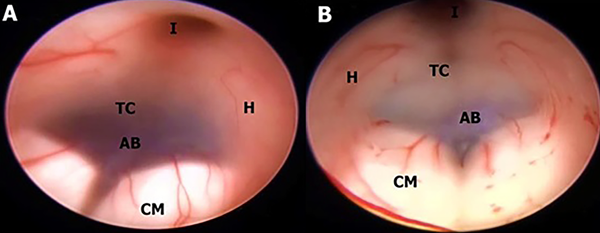

En este estudio fueron halladas 10 variedades anatómicas del piso anterior del tercer ventrículo, las cuales son en orden de frecuencia: piso opaco o grueso 54,90% (Figura 1), piso parcialmente borrado 29,41% (Figura 2), intervalo prepontino pequeño 23,53% (Figura 3), piso estrecho 17,65% (Figura 4 A-B), piso herniado 17,65% (Figura 5), piso delgado 11,76% (Figura 6), basilar elevando el piso 1,96% (Figura 4C-D), adherencias interhipotalámicas 3,92% (Figura 7), fenestración espontánea 1,96% (Figura 8), y piso sin reparos anatómicos 1,96% (Figura 9). Las primeras 7 según la descripción de Sughrue, a la cual se sustituye banda premamilar por adherencias interhipotalámicas, descriptas por Phillips4, fenestración espontánea al hallarse ausencia de PTV u ostomía espontánea como en la Fig. 8, reportada por Parmar5, y se introduce otra categoría no reportada, piso sin reparos anatómicos cuando no se pueden diferenciar los cuerpos mamilares ni el receso infundibular. En la mayoría de los casos se detectaron 2 o más variedades.

Figura 1: Piso opaco en diferentes etiologías de hidrocefalia. A; Mujer de 74 años con estenosis acueductal en cuya imagen endoscópica no se puede visualizar estructuras de la cisterna interpeduncular a través del piso. B; Acercamiento de A constatándose opacidad. C-D Hombre de 16 años con hidrocefalia congénita, portador de DVP, con disfunción de la misma, con agenesia incompleta del Septum Pellucidum y presencia de Cavum septum Pellucidum en C y piso opaco y estrecho más CM de tipo kissing en D. E; Masculino de 49 años con antecedente de meningitis tuberculosa, con hidrocefalia comunicante, con disfunción de DVP. F; Hombre de 49 años con HIC talámico izquierdo más hemoventrículo. Se realiza lavado endoscópico y evacuación de HIC por estereotaxia. Se evidencia piso grueso con petequiado ependimario a nivel del tegmentum y coágulo obliterando acueducto de Silvio. CM kissing. C caudado; CM cuerpo mamilar; Co coágulo; CSP cavum septum pellucidum; FM foramen de Monro; Fx fórnix; H hipotálamo; I Receso infundibular; LT lámina terminalis; Q quiasma; R receso premamilar; SP septum Pellucidum; T tegmentum mesencefálico; TC Tuber cinereum.

Figura 2: A Masculino con hidrocefalia crónica, posterior a craniectomía descompresiva por TEC grave. Muestra piso parcialmente opaco que permite ver la AB inmediatamente anterior a los CM, pero no en toda su extensión. CM Split. B; Hombre de 49 años con HIC talámico derecho más hemoventrículo, se realiza evacuación estereotaxica de HIC y endoscópica de hemoventrículo, TVE y septostomía. El piso es mayormente opaco, excepto el área adyacente a los CM, a través del cual el ápex basilar es apenas visible. Se puede observar un petequiado en las paredes ventriculares y CM de configuración kissing. AB arteria basilar; CM cuerpo mamilar; H hipotálamo; I Receso infundibular; TC Tuber cinereum.